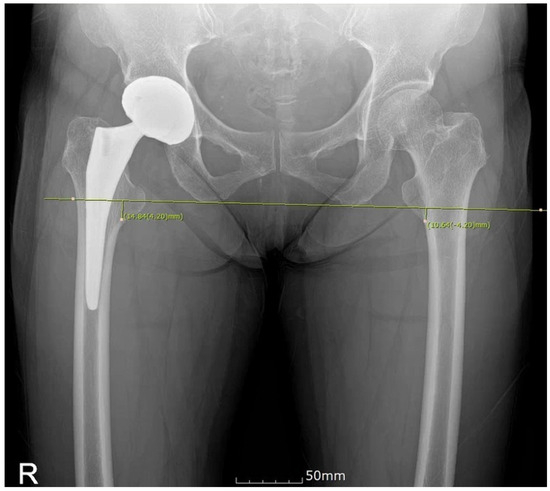

Radiographic evaluation of LLD was conducted using the picture archiving and communication system (PACS), which has same version of program between two different hospitals. Leg length was measured on an anteroposterior view of the hip joints taken with both lower legs internally rotated by 15°. The measurement was based on the difference between the inferior margin of the ischial tuberosity in the pelvic bone and the lowest point of the lesser trochanter [9]. To reduce inter-observer reliability bias, one surgeon (Jihyo H) measured whole images. The accuracy of mLLD obtained through the new EKG lead attachment site was verified by comparing it with postoperative LLD (xLLD), measured from bilateral pelvic radiographs, with intraoperative LLD (mLLD), displayed on the Mako monitor (calculated by inputting the positions of the check point inserted into the femoral greater trochanter and the EKG lead attached to the lateral femoral epicondyle) after inserting the implant. These results were compared with LLD outcomes in an equal number of patients who underwent THA using the intrapatella landmark and those who underwent conventional THA. Moreover, as anatomical landmarks may be less distinct in obese patients, potentially introducing bias, a comparison was conducted with patients having a BMI of 25 or higher. Radiographic evaluations were performed by the operating surgeons.

After changing the EKG lead attachment site in Mako-assisted THA from the intrapatella landmark to the lateral femoral epicondyle, we compared intraoperative LLD measurements (mLLD) (Figure 2) with postoperative X-ray-based LLD measurements (xLLD) using PACS (Figure 3). The mean mLLD was 4.8 mm (−6–12 mm), while the mean xLLD was 1.43 mm (−7.43–11.63 mm), showing that X-ray-based LLD measurements yielded better results than mLLD (Table 2).

Figure 3. Postoperative LLD (xLLD) measured using PACS.